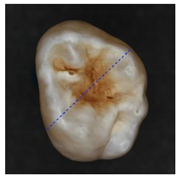

The classification model generated by the fine kNN algorithm was used to classify the fissural systems of five additional teeth, which were not included in the training and evaluation of the algorithm (Table 3). The projection maps show that the classified enamel state is in good agreement with the PLM images in the histologically validated area: Stained samples show a nearly homogeneous distribution of the predicted enamel state “stained”. However, some clearly circumscribed regions away from the histologically validated area are classified as “stained lesion”. Stained lesion samples exhibit a more heterogeneous distribution of enamel health states: A large proportion of fissural areas are classified as “stained lesion”; however, there are numerous “stained” regions of varying sizes dispersed in between.

Table 3.

Clinical simulation of enamel health predictions using HSI-based automated classification as a decision-support system. Five additional teeth (two stained [(a) and (b)], three stained lesion [(c) through (e)]) were imaged and classified by the previously trained fine kNN classification algorithm (i.e., the samples in this table were not included in algorithm training). Stained sound enamel is displayed green, whereas lesions (stained or unstained) are displayed red. Polarization microscopy images from each tooth’s sectional plane (dotted lines) serve as reference. All scale bars = 1 mm.